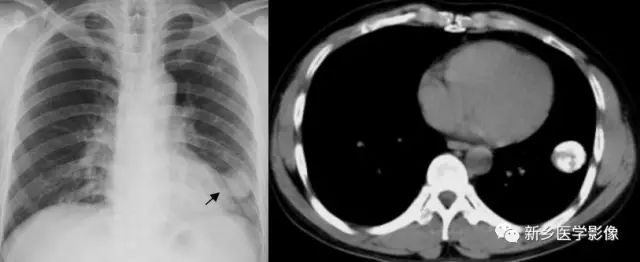

左肺结核球X线胸部正位片、CT纵隔窗图

a. X线胸部正位片 b. CT纵隔窗示钙化(↑)